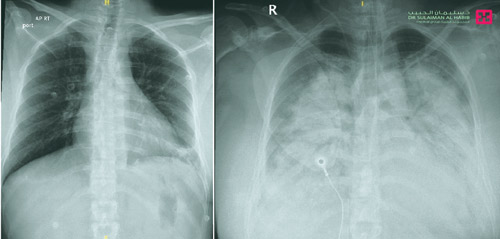

وقال د. فهد بن عبد الله الحماد استشاري العناية المركزة، إن الحالة الأولى لسيدة ثلاثينية أُسعفت إلى طوارئ المستشفى، وتوقف قلبها بمجرد وصولها، فتم إنعاشها وتحويلها إلى العناية المركزة، ثم وضعت على جهاز التنفس الصناعي ، إلا أن نسبة الأكسجين في دمها لم ترتفع إلى المستويات المطلوبة، وعانت أيضاً من هبوط حاد في القلب وفي وظائف التنفس، بالإضافة إلى حموضة شديدة بالدم. وتواصلت معاناتها مع هذه الأعراض على الرغم من دعم القلب والتنفس بجرعات عالية من الأدوية والأكسجين، فوضعت المريضة على الإيكمو لمدة «5» أيام، وبدأت حالتها الصحية في التحسن ، حيث استعاد القلب نشاطه تدريجياً وقدرتها على التنفس، الأمر الذي انعكس إيجاباً على معدلات الأكسجين في دمها، وقبلها كانت قد استعادت وعيها بالكامل ولله الحمد.

أما الحالة الثانية فقد أسعفت إلى المستشفى في حالة حرجة، بعد إصابتها بهبوط حاد في ضغط الدم، ووظائف التنفس بسبب الضعف الشديد في القلب، وتم تحويلها إلى العناية المركزة، وهي على جرعات عالية من الأدوية الداعمة لضغط الدم، وعلى الرغم من ذلك لم تستقر حالتها، حيث تواصلت معاناتها مع هبوط في ضغط الدم ووظائف التنفس وضعف القلب، فتم وضعها على جهاز الإيكمو لمدة أسبوع، وتقديم العلاجات اللازمة لها ، مما أسهم في استعادة قلبها لنشاطه الطبيعي ولله الحمد، ومن ثم خرجت إلى منزلها وهي بحالة صحية جيدة.